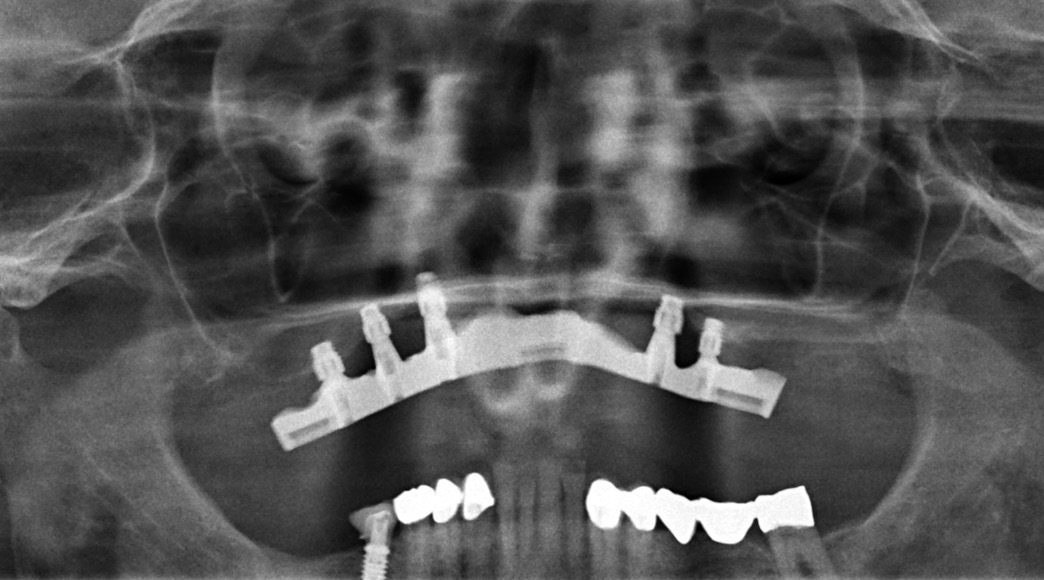

Implantattherapie: Kurze Implantate als Ausweg

Die Implantatpositionierung war eine Herausforderung. Die Knochenblöcke haben eine durchschnittliche Höhe von 1 cm. Normalerweise wird versucht, die Implantate so zu inserieren, dass der unter dem Transplantat befindliche, ortsständige Knochen eingebunden wird. Aufgrund der relativ lockeren Verbindung des Transplantates mit dem Knochen bestand die Gefahr eines Abhebens des Knochenblockes bei der Insertion. Zudem müssen die unvermeidbaren Resorptionen am allogenen Block – vergleichbar mit natürlichem Knochen – bedacht werden, die nach Erfahrung des Autors zirka 10 bis 15 Prozent betragen [Nilius, M. in process]. Dieser Verlust ist bei der Überlegung zum Implantatsystem einzubeziehen.

Kurze Implantate

Der vorgestellte Fall zeigt die Möglichkeiten einer kompletten absoluten Kieferkammerhöhung mit allogenen Blöcken. Der Umfang der knochenaufbauenden Maßnahmen im vorgestellten Patientenfall ist in dieser Art bisher nur selten vorgenommen worden. Die Verwendung patientenspezifischer allogener Knochenblöcke hat viele Vorteile gegenüber autologen Knochenblöcken, z. B. keine Entnahmestelle und verkürzte Operationszeit. Zudem spricht die genaue Passform von gefrästen Blöcken besonders bei komplexen Defekten für das Vorgehen. Grundsätzlich ist der Erfolg einer solchen Therapie von vielen Faktoren abhängig. Wichtig ist nicht nur die knöcherne Fixierung des allogenen Transplantates, sondern die Weichgewebedeckung. Diese besteht bei der Erstoperation zunächst in einer Dehnung und spannungsfreien Adaptation der mukogingivalen Reserven mit Unterstützung einer Membran bzw. geschützten Abdeckung des Augmentates. Ist dieses Ziel erreicht, besteht das sekundäre Ziel in einer Verdickung und Optimierung der Implantat umgebenden Weichgewebestruktur. Nur so kann nach der Einheilung ein Langzeiterfolg erzielt werden. Zudem muss nach Einheilung der Transplantate wohlüberlegt das passende Implantatsystem gewählt werden, um die knochenaufbauenden Maßnahmen nicht zu gefährden. Hier bieten kurze Implantate (SICmax kurze Implantate, SIC invent oder vergleichbare) eine gute Alternative und in vielen Situationen den Ausweg. Das Implantat verfügt über eine spezielle Struktur. Der krestale Microthread ist sehr gut für D2-D4 Knochendichte geeignet und komprimiert das Implantat auch im rekonstruierten Knochen.